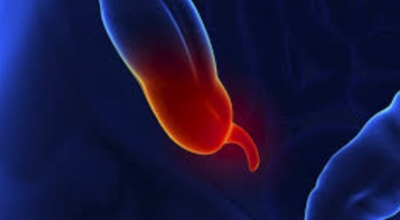

맹장염은 맹장 끝 충수돌기에 생기는 염증이라고 볼 수 있다고 하며, 보통 맹장염으로 알려져 있기는 1개 실질적으로는 부위가 충수돌기이기 때문에 의학 용어로는 충수염이라고 부르는 단어가 더욱더 정확하다고 해요. 맹장염(충수염)은 한국 사람들이 수술을 진행하는 질병 5위라고 불릴 정도로 수시로 발생하며 매해 약 10만 명 정도가 수술을 받을 만큼 통상적으로 생기는 질환이예요.

복통과 소화불량으로부터 시작하는 초기 맹장염 증상이 나타나는데 많은 분들이 소화기 계통 질환으로 오인해 약만 먹고 그냥 지나치는 경우가 많다고 해요. 대장이 시작되는 부위를 맹장이라고 하며 그 끝부분에 약 5~10cm 정도의 길이로 꼬리처럼 달린 구조물을 충수 또는 충수돌기라고 그렇지만, 통상적으로 말하는 맹장염은 이 충수가 막히거나 눌려서 염증이 발생해 통증이 생기게 되는데 심할 경우 터지는 경우가 나타나기도 해요.